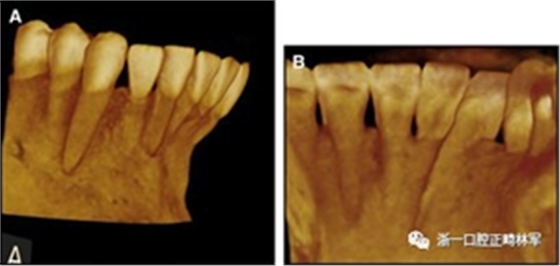

臨床檢查顯示固定保持器完好,弓絲沒(méi)有斷裂(圖13)。在下頜右側(cè)中切牙唇側(cè)和鄰近側(cè)切牙的舌側(cè)注意到有牙齦退縮。這些牙齒在退縮方向上存在顯著的扭矩差異。下頜的左側(cè)尖牙頰側(cè)錯(cuò)位,而右側(cè)尖牙舌側(cè)傾斜。三維射線照片證實(shí)了下頜右側(cè)尖牙面?zhèn)妊啦酃菃适?,右?cè)中切牙的喪失程度較輕。右側(cè)側(cè)切牙根也從舌側(cè)骨面上扭轉(zhuǎn)出來(lái)(圖14)。

圖14.三維立體圖像:A,面部和B,切牙根部的舌側(cè),剛?cè)〕龉潭ㄉ鄠?cè)保持器后。

再治療的目標(biāo)是使牙齒恢復(fù)到冠和根的正常位置,并刺激退縮和牙根暴露區(qū)域新骨的形成。牙周手術(shù)和正畸聯(lián)合治療是完成這些所必需的。